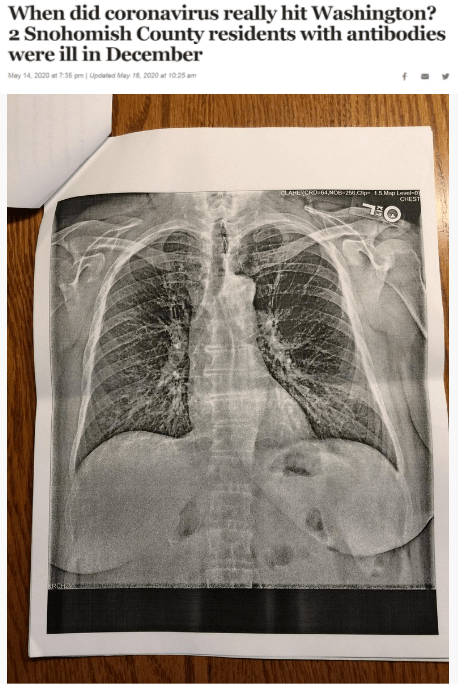

据《西雅图时报》去年5月14日报道 , 华盛顿州斯诺霍米什县的两位居民在2019年12月出现类似新冠肺炎的症状 , 之后对他们的新冠病毒抗体检测呈阳性反应 。 这一结果表明 , 新冠病毒可能比想象中更早在当地出现 。

文章图片

△《西雅图时报》报道截图(题图中的X光片显示其中一位斯诺霍米什县居民的肺部“过度充气”并出现“线性混浊” 。 医生认为 , 这可能是叠加上呼吸道肺部感染的表现 。 )